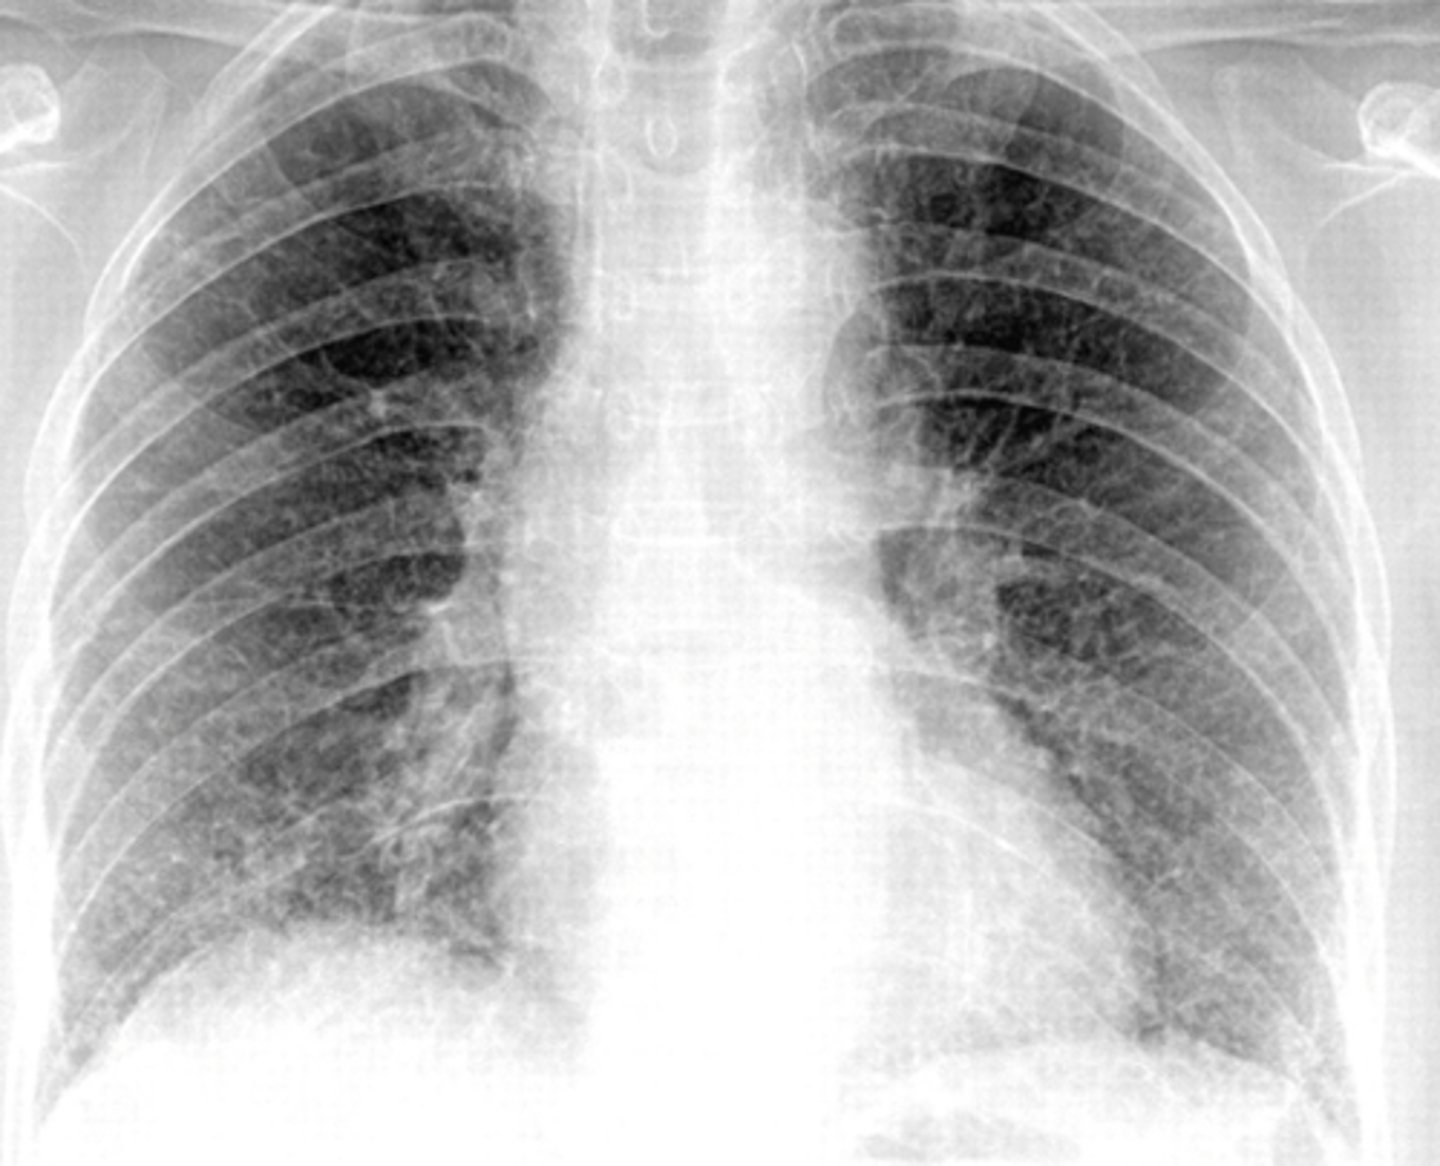

An HIV patient presents with a nonproductive

cough and a CXR showing diffuse interstitial

infiltrates. What diagnosis should you be thinking

of?

Pneumocystis jiroveci pneumonia (PCJ) formerly known as Pneumocystis pneumonia (PCP)

What does PCP look like on a radiograph?

Classic is bilateral diffuse symmetric finely granular opacities/reticular-interstitial airspace disease